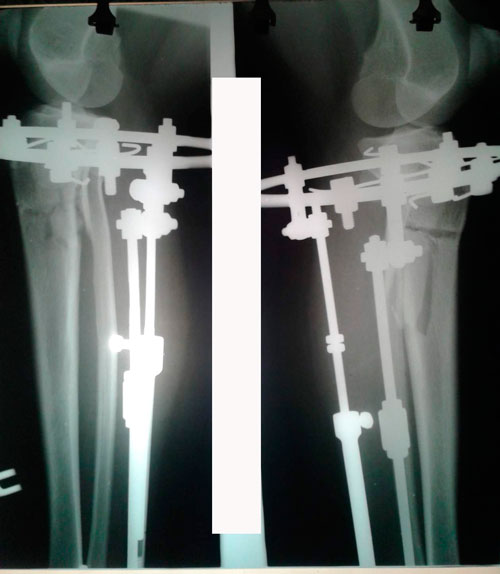

Здравствуйте уважаемый Николай Николаевич и Наталья!

Отправляю вам контрольные рентген-снимки и фото ножек. Со дня снятия прошло 50 дней.

Здравствуйте, Наталья! По рентгену, всё отлично! разрешено всё без ограничений! Исключить: беременность в течении первых 6 месяцев.

Спасибо за фото ножек! не забывайте про наш форум, пишите отзывы, выставляйте фото красивых ножек! Это для нас важно, мы гордимся своей работой!